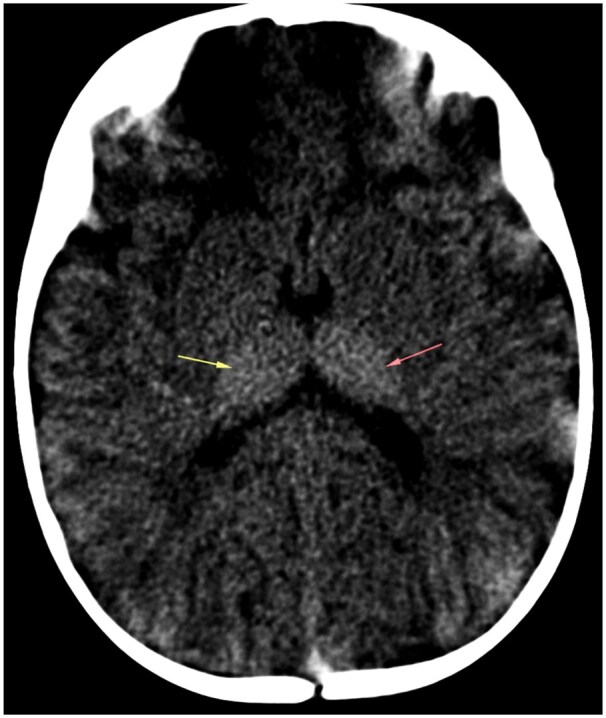

单唾液-四己糖神经节苷脂,也被称为婴儿GM1神经节苷脂病,是一种常染色体隐性溶酶体储存疾病,由GLB1基因突变引起,该突变阻止了β-半乳糖苷酶的工作。我们讨论了一例婴儿GM1神经节脂质沉积症,其表现为异常的身体运动,背部和臀区广泛的皮肤黑色素细胞增多,面部特征粗糙,以及大头畸形。影像学表现为第二、第三、第四腰椎前下喙状突起,非对比CT显示双侧丘脑高密度。在T2加权图像上,白质和皮质下U纤维持续高信号强度,表明双侧丘脑体积大,T2低,髓鞘形成明显受损。β-半乳糖苷酶活性降低证实了诊断。

Mono-sialo-tetra-hexosylganglioside, also known as infantile GM1 gangliosidosis, is an autosomal recessive lysosomal storage disorder caused by a mutation in the GLB1 gene that stops the β-galactosidase enzyme from working. We have discussed a case of infantile GM1 gangliosidosis which presented with abnormal body movements, extensive dermal melanocytosis over back and gluteal region, coarse facial features, and macrocephaly. Radiological features included antero-inferior beaking of second, third, and fourth lumbar vertebrae, bilateral hyperdense thalami on non-contrast CT. On T2-weighted images, there is a persistently high signal intensity of the white matter and subcortical U fibres, which indicates bilateral bulky thalami with T2 hypointense and significantly impaired myelination. Reduced β-galactosidase activity verified the diagnosis.